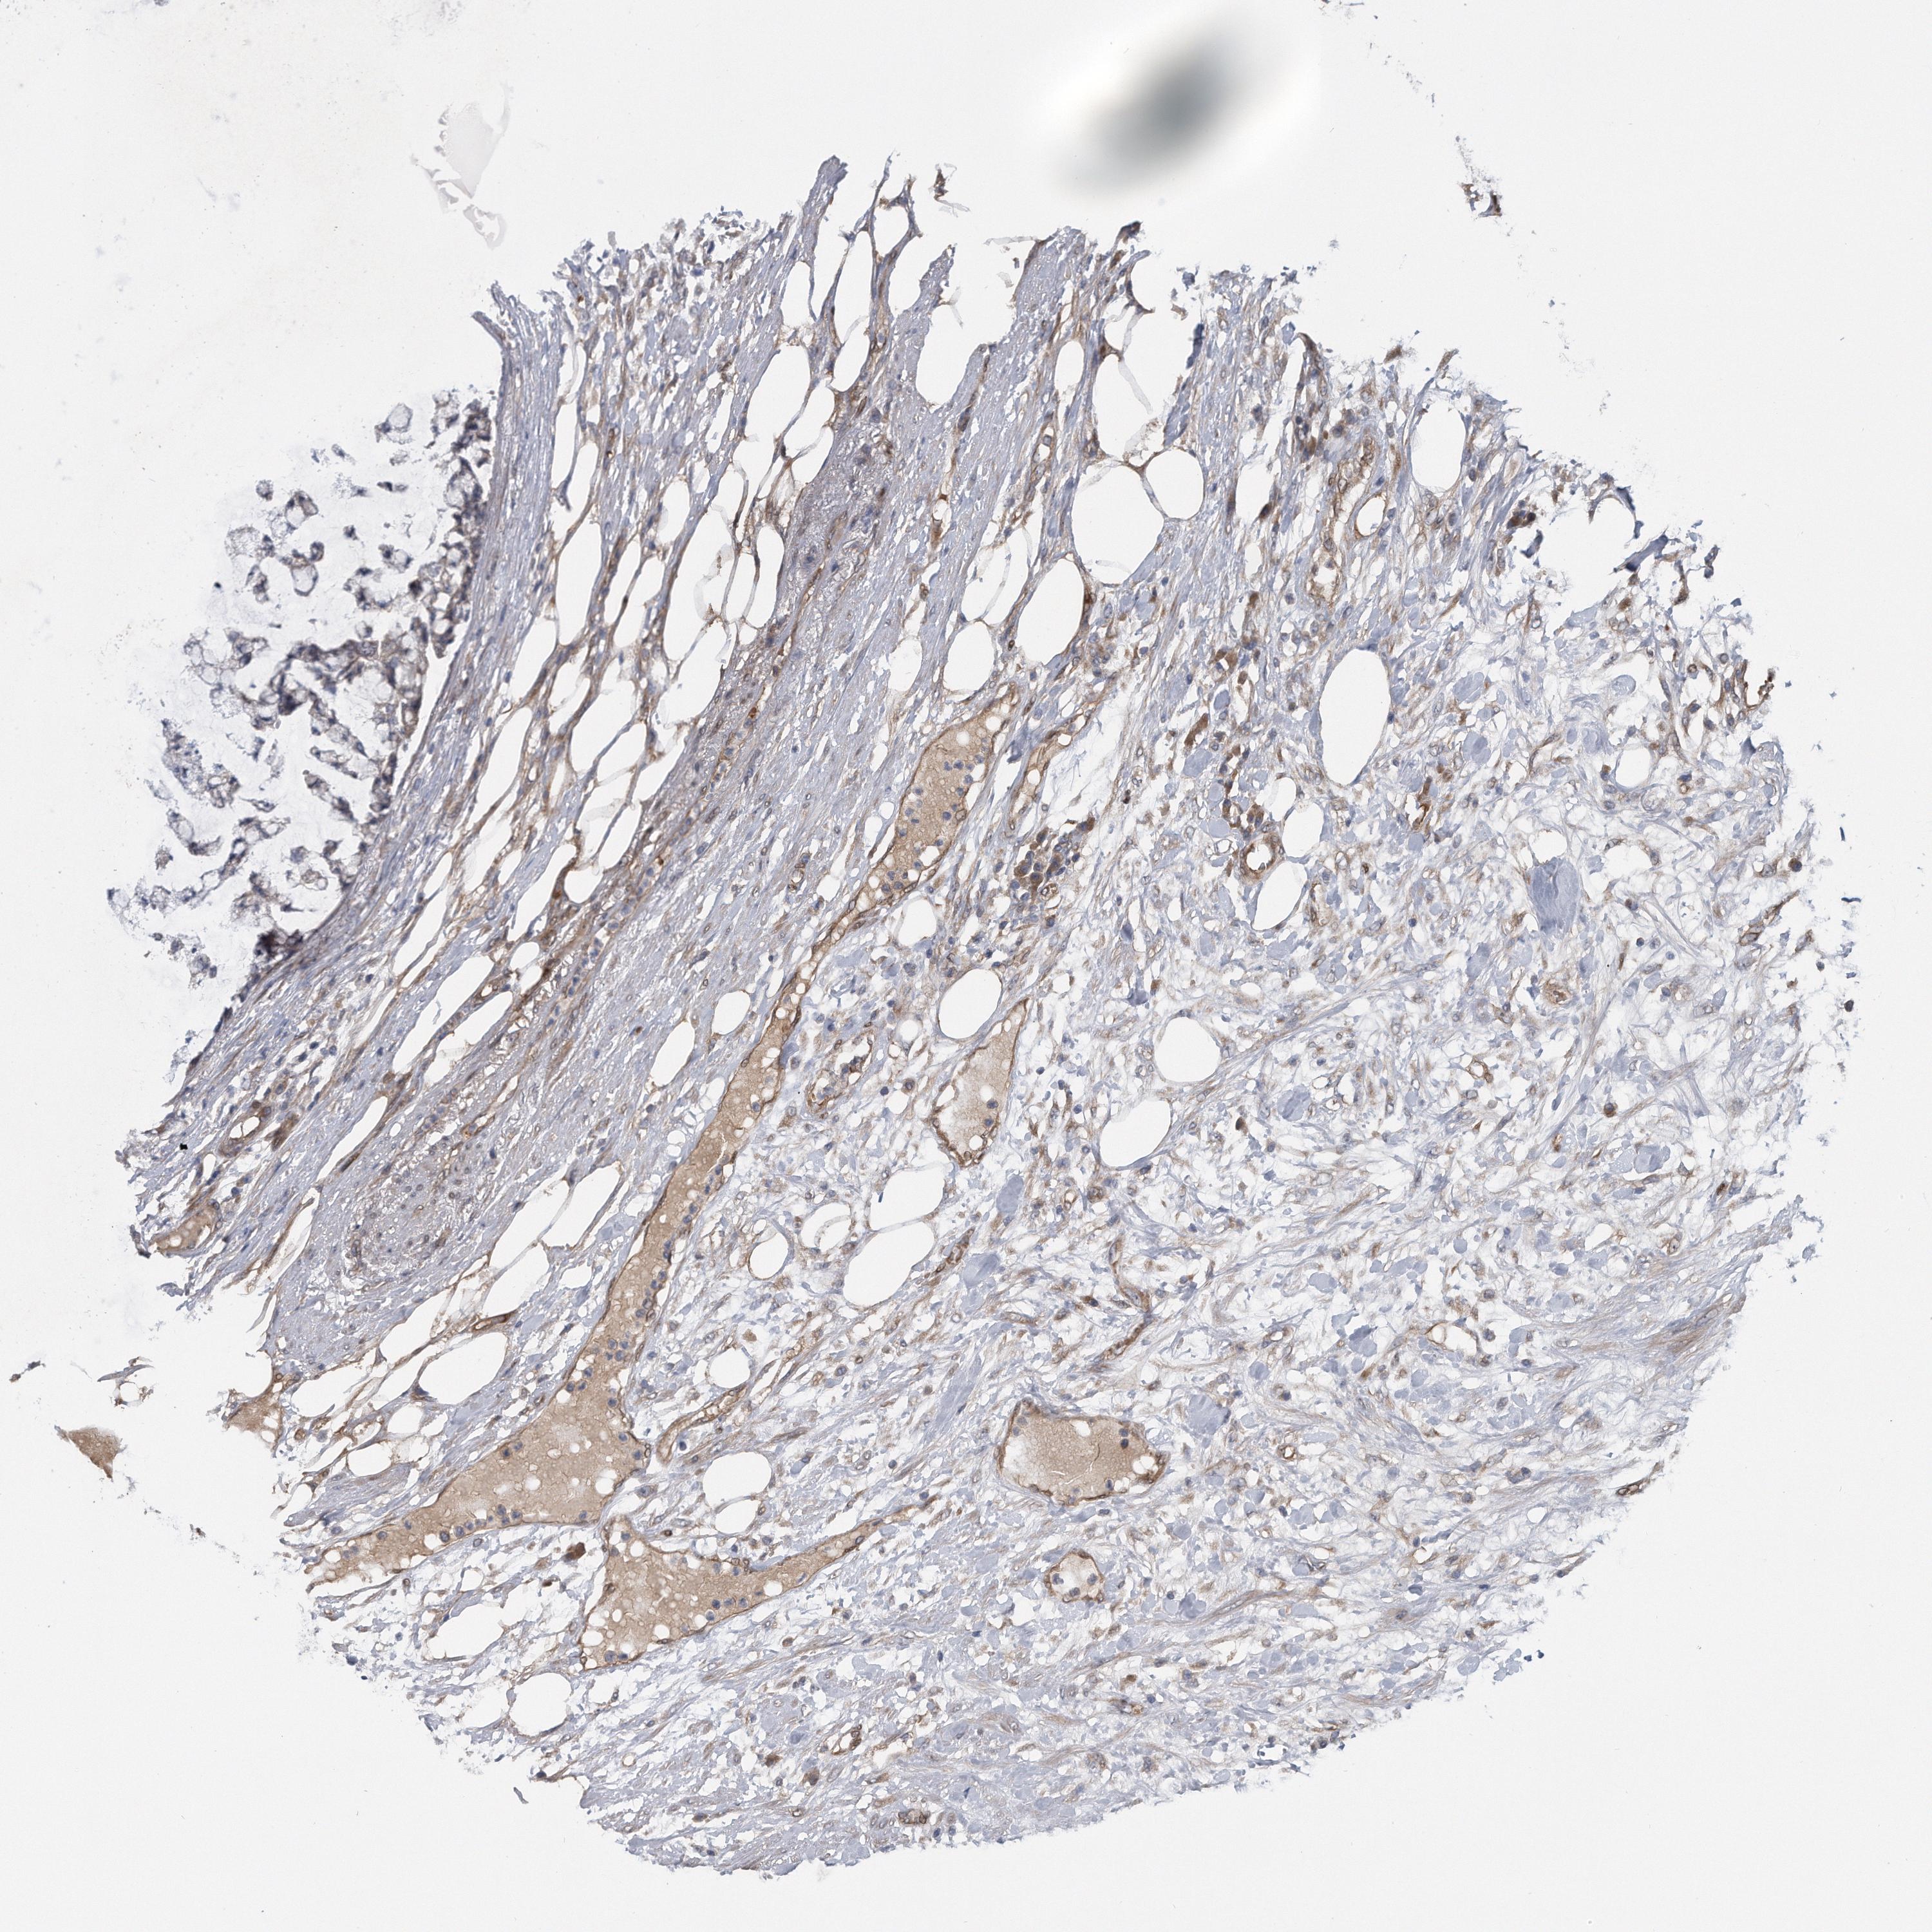

COLON ADENOCARCINOMA (VALIDATION) - Interactive survival scatter ploti

The Survival Scatter plot shows the clinical status (i.e. dead or alive) for all individuals in the patient cohort, based on the same data that underlies the corresponding Kaplan-Meier plots. Patients that are alive at last time for follow-up are shown in blue and patients who have died during the study are shown in red.

The x-axis shows the expression levels (FPKM) of the investigated gene in the tumor tissue at the time of diagnosis. The y-axis shows the follow-up time after diagnosis (years). Both axes are complimented with kernel density curves demonstrating the data density over the axes. The top density plot shows the expression levels (FPKM) distribution among dead (red) and alive patients (blue). The right density plot shows the data density of the survived years of dead patients with high and low expression levels respectively, stratified using the cutoff indicated by the vertical dashed line through the Survival Scatter plot. This cutoff is automatically defined based on the FPKM cutoff that minimizes the p-score. The cutoff can be changed by dragging the vertical line or by entering a cutoff value in the square labeled "Current cut-off".

Under the Survival Scatter plot the p-score landscape (black curve; left axis) is shown together with dead median separation (red curve; right axis). Dead median separation is the difference in median mRNA expression between patients who have died with high and low expression, respectively. It is calculated as follows: median FPKM expression of dead patients with high expression - median FPKM expression of dead patients with low expression. This is intended to aid the user in visually exploring custom cutoffs and the associated p-scores and dead median separation.

Individual patient data is displayed and can be filtered by clicking on one or more of the category buttons on the top of the page. Categories describing expression level and patient information include: high, low, alive, dead, female, male and tumor stages. The scale of the x-axis can be toggled between linear and log-scale by clicking on the "x log" button. Mouse-over function shows TCGA ID, patient information and mRNA expression (FPKM) for each patient.

& Survival analysisi

Kaplan-Meier plots summarize results from analysis of correlation between mRNA expression level and patient survival. Patients were divided based on level of expression into one of the two groups "low" (under cut off) or "high" (over cut off). X-axis shows time for survival (years) and y-axis shows the probability of survival, where 1.0 corresponds to 100 percent.

ZNF79 is potential prognostic, high expression is unfavorable in Colon Adenocarcinoma (validation)

Best expression cut offi

Based on the FPKM value of each gene, patients were classified into two groups and association between prognosis (survival) and gene expression (FPKM) was examined. The best expression cut-off refers the FPKM value that yields maximal difference with regard to survival between the two groups at the lowest log-rank P-value. Best expression cut-off was selected based on survival analysis .

When clicking on this number, the vertical dashed line indicating cut-off, the interactive survival plot, and the Kaplan-Meier curve will be adjusted to show results based on the best expression cut-off.

: 9.21

Average pTPM 7.9

Number of samples 486